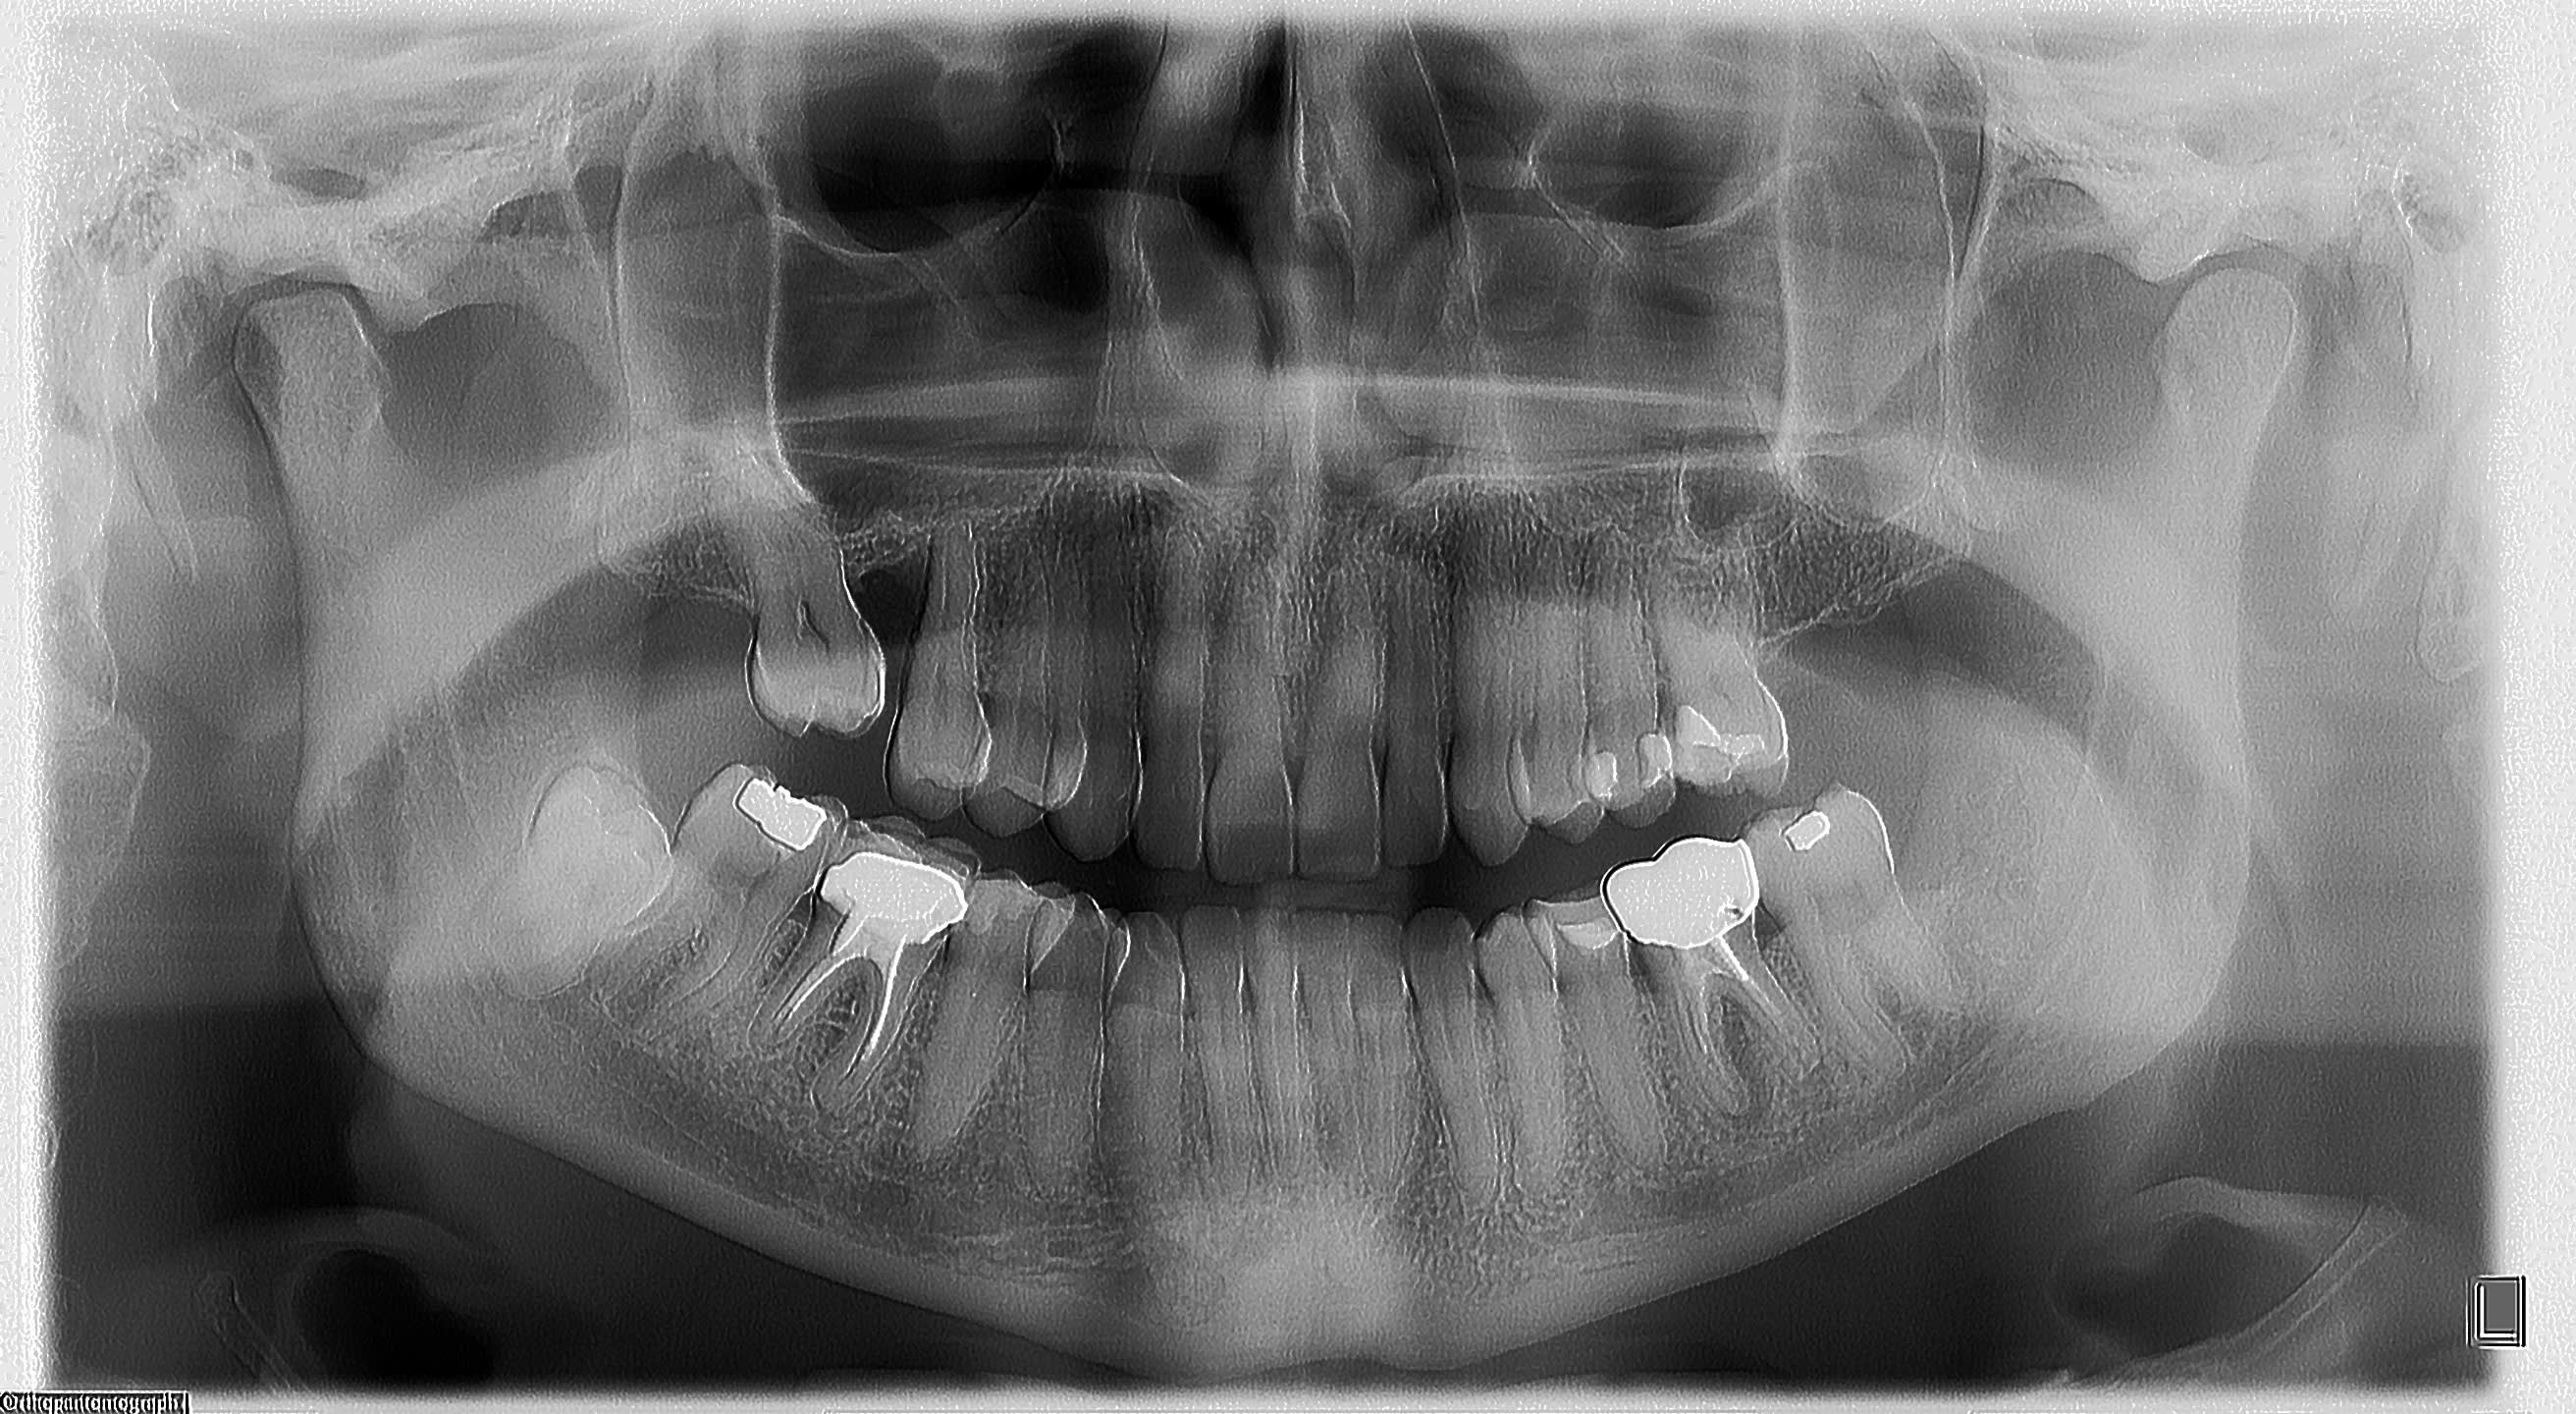

Je fais la radio de contrôle et je vois un gros dépassement d'hyca ,juste injecté à la seringue, pas de lentulo,au niveau de la lésion apicale visible radiologiquement.

Bonjour si on pouvait voir la radio ce serait un plus. Le dépassement intéresse t il le nerf dentaire? Sinon en général ce genre d'affaires moins on y touche mieux on se porte. Car tu risques de perturber encore plus. Il vaut mieux attendre et surveiller.

ceci dit , puisqu'on a pas de radios

Le canal dentaire n'est pas en cause, l'hyca est cantonné dans la lésion qui remonte vers la furcation.

Je fais parvenir les radios panoramiques .

En revanche les apex semblent grands ouverts...

Dans tout ça ce qui me dérange le plus c est la distribution d antibio façon Haribo, sans respect des recommandations et la pano post opératoire...

quand tu fais un depassement sur une de ces dents, tu n'as jamais la trouille d'une atteinte du canal mdbulaire par le produit d'obturation?

Et une pano ici est totalement justifiée. L'irradiation d'une pano c'est deux retroalveloaitres et demi, alors le rayonnement , hein, dis, hein, c'est que dalle devant ceux et celles qui mitraillent en retro....